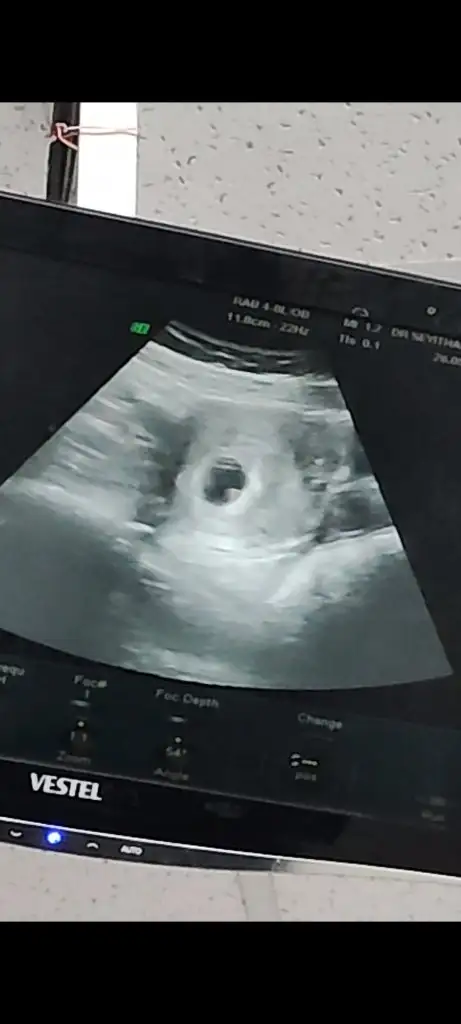

Kuzum yolku göremedim diye de dert ettim ben ama şunu anladım aynı hastanede iki farklı doktora gittim birindeki ultrason cihazı daha iyiydi ilk gittiğim doktor keseyi görememişti bile saçma şekilde bak rahmin boş gebelik emaresi yok gibi saçma cümleler kurmuştu. İki gün sonrası başka hasteneye gittiğimde ise kendim bile ne güzel şekilli şüküllü kese be demiştimBebişi zaten umut etmedim ama yolk bari az gözükür sanmıştımkanama yok şükür zaten progestan fitil oksapar kullanıyorum bakalım sabırla bekleyeceğim